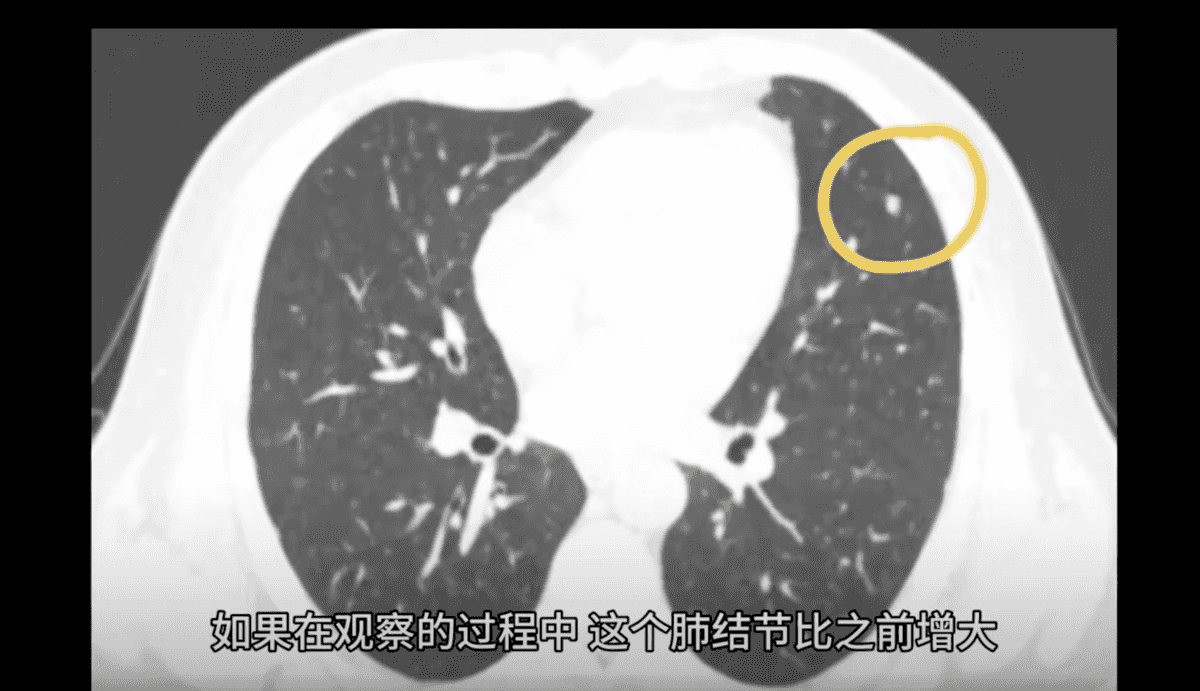

認證為「心胸外科副主任醫師」的山西醫科大學第一醫院胸外科醫療組組長閆曉亮博士2月6日發影片,講解肺磨玻璃結節和實性肺結節哪種更危險。

他說,很多人體檢時發現肺部有結節,有的是純磨玻璃肺結節,有的是混雜密度磨玻璃結節,有的是實性結節。相關的研究發現,混雜密度磨玻璃肺結節的惡性概率(肺癌率)約為63%。如果都是惡性結節,實性結節預後最差。

由於有肺結節的人眾多,網絡上出現不少所謂去除結節的「偏方」。對此,認證為「上海三甲醫院呼吸內科副主任醫師」的胡洋在1月8日的影片中說,查出肺結節,沒有特效藥可治。患者只有兩條路:隨訪和手術。肺癌性的結節用甚麼藥都沒有用的。